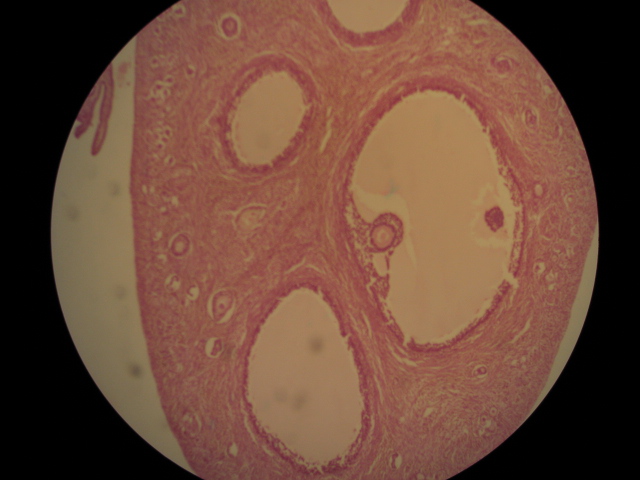

| Tertiary follicle | What type of follicle is this one?,  |